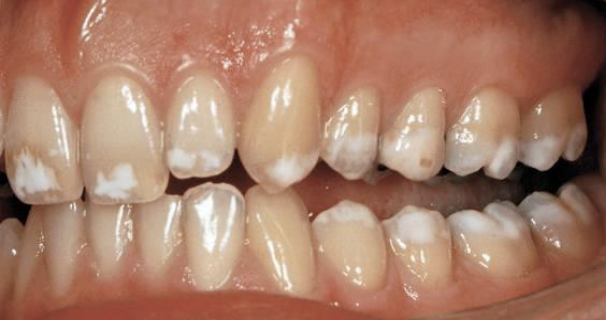

AD, AR, X-linked; both deciduous and permanent dentition are diffusely involved, affects enamel (soft, thin, easily damaged, susceptible to decay), dentin is exposed

amelogenesis imperfecta (AI)

Types of AI

hypoplastic (pitted), hypomaturation/ hypocalcification (snowcapped) AI with taurodontism

what type of AI

hypomaturation (snowcapped)

Clinical appearance of AI

yellow-brown to white pitted lesions, open bite, loss of contact

ingestion of excess amount of fluoride, retention of amelogenin protein in enamel, hypomineralization creating chalky white areas, must be bilateral symmetrical distribution with previous exposure to Fl

fluorosis, mottled enamel